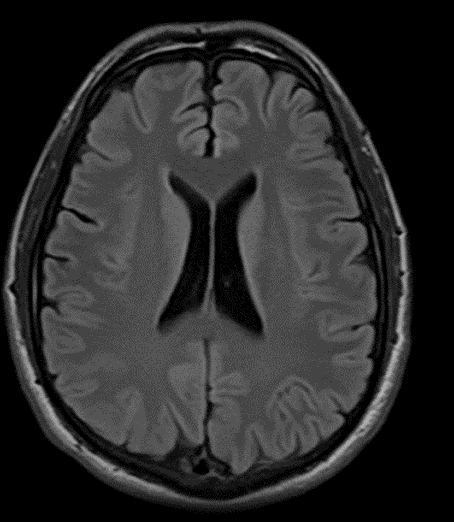

先ほど示した症例の経過観察後のMRI画像

血腫の量が少ない&症状が軽微の場合は外来通院治療でも治癒することが多い

急性硬膜下血腫と異なり、じわじわと血液が滲み出してくる慢性硬膜下血腫は、安静に過ごすことでまた自然と吸収してくれることがあります。

穿頭(せんとう)血腫除去術後

血腫は除去されている

術後から症状は改善され、退院。